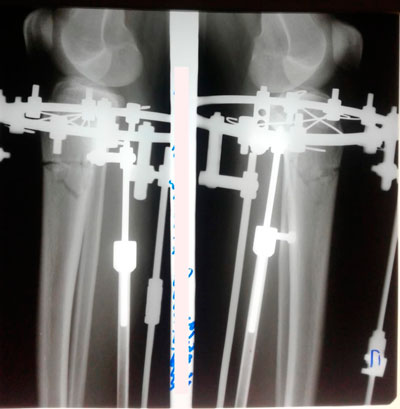

Исходник - 16 лет.

Дата операции - 30.04.2019г.

Дата снятия аппаратов - 23.07.2019г.

Срок сращения - 83 дня.